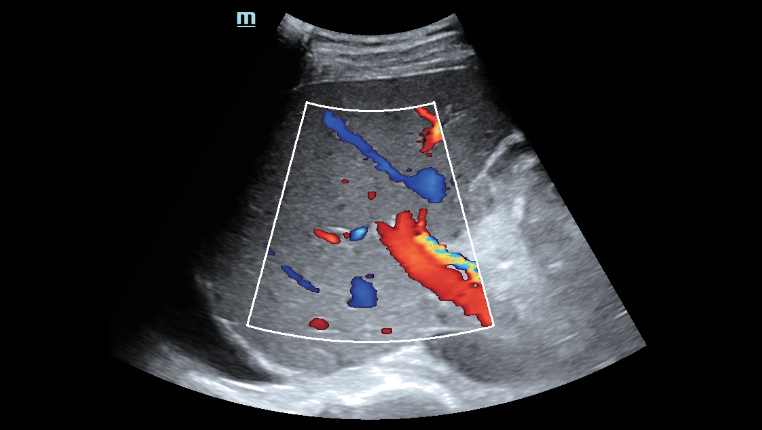

â A excelente qualidade de imagem e as fun??es de ultrassom permitem uma avalia??o abrangente da morfologia e hemodin?mica do fÃgado.

â A excelente qualidade de imagem e as fun??es de ultrassom permitem uma avalia??o abrangente da morfologia e hemodin?mica do fÃgado.